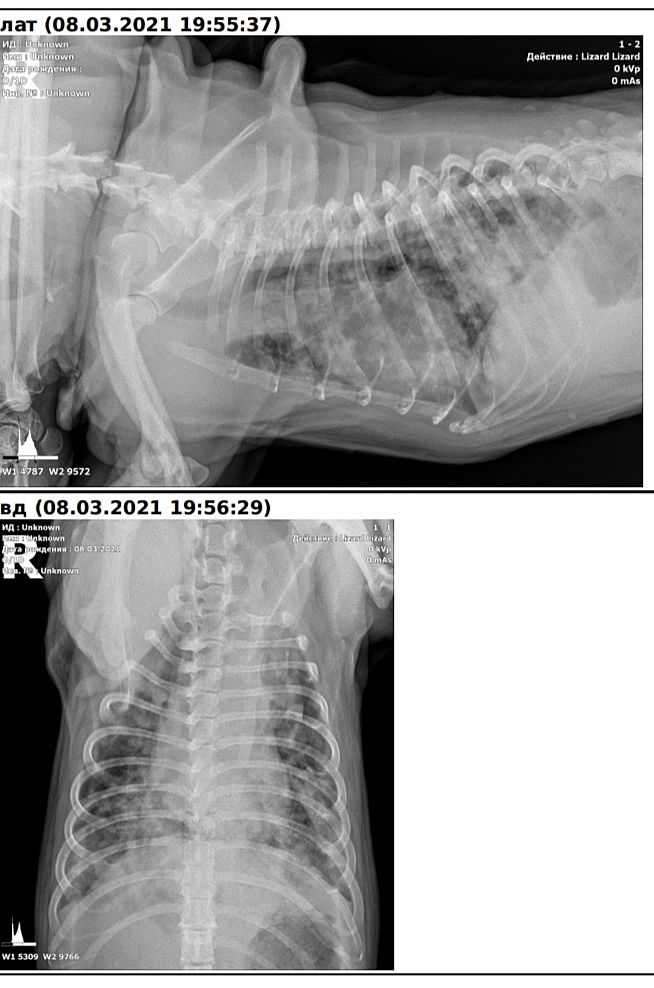

Вопрос пульмонологам/ветеринарам. Фото рентгена

Девочки, форумчаники, если среди вас есть пульмонолог/ветеринары, скажите, пожалуйста, что вы видите на снимке моего собаки? Все плохо? Ценен для меня любой комментарий по существу. Спасибо

Вряд ли вы таких узких спецов здесь найдёте. Я медик, но по другой части. Хотя немного касаемся разных заболеваний. Вот как раз вчера нам показывали снимки лёгких человека. Из тех, что показывали, визуально похоже на фиброз. Вот эта сеточка по всем лёгким. Но это так, чисто внешнее сравнение с тем, что видела.

Метастазы

Не нашли центральную опухоль. Делали УЗИ, рентген. Вот и закрались у меня сомнения. Это предположение врачей. Назначили собаке антибиотик и преднизолон.